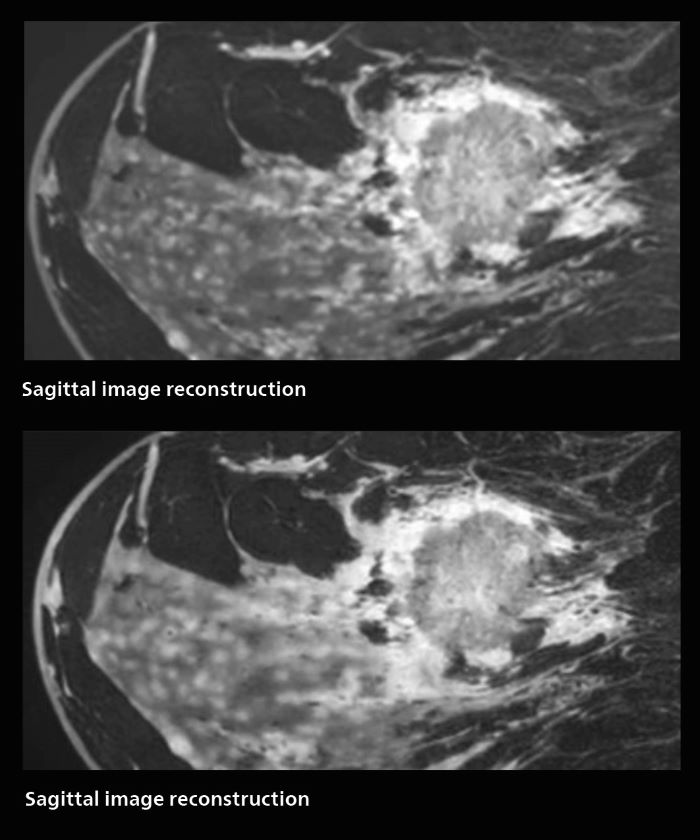

With SmartSpeed, Kumamoto Chuo Hospital also has the ability to use EPI diffusion-weighted imaging (EPICS-DWI) with Compressed SENSE, which is an important step forward according to Dr. Katahira. “Before, our EPI diffusion was performed using SENSE, but now with Compressed SENSE it is possible to obtain very clear images,” he says. He also describes the benefit of being able to perform 3D diffusion-weighted imaging. “Previously, we only had DWI images in one direction to make a diagnosis. Now, we can do something that was not possible before: performing a DWI volume acquisition so that multiplanar reconstruction can be used, allowing us to look at scan results from all directions to make the diagnosis,” Dr. Katahira says. “What used to be a diagnosis based on just cross-sectional images, can now be based on a volume image. This is a dramatic improvement for us, because it is now possible to look at slices in various cross section directions. For example, the presence or absence of venous invasion is very important in rectal cancer patients, because venous invasion can cause metastasis in the future. The ability to reconstruct images according to the direction of the blood vessels, allows us to see venous infiltration more realistically, which is a world of difference from what we were used to.”

In this patient MRI was done to help in diagnosing the depth of invasion. Performed on Elition X.